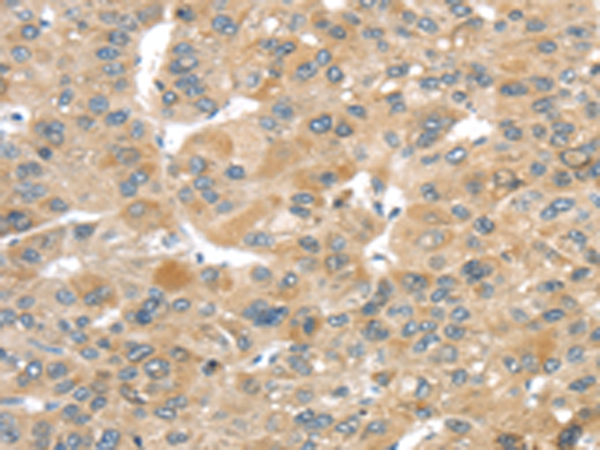

分类: 科研抗体货号: P08902别名: EG1; magicin; 1500003D12Rik应用: WB,IHC反应种属: Human, Mouse, Rat